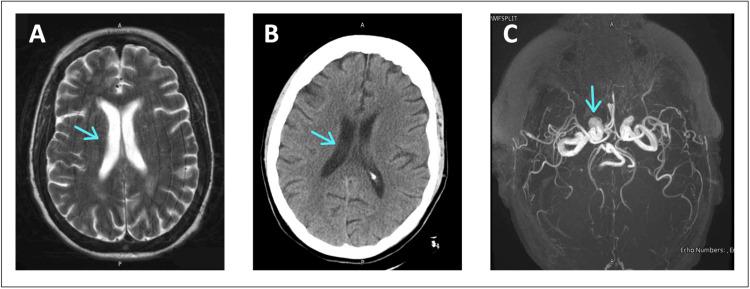

Neurotoxicity can develop as a side effect of valacyclovir in patients with renal disease, especially without a renally adjusted dose. We present a 56-year-old female with end-stage renal disease (ESRD) on hemodialysis (HD) who presented to the emergency room (ER) with agitation and confusion and was found to have valacyclovir-associated neurotoxicity (VAN). Five days prior, she had been prescribed the standard treatment of 500 mg valacyclovir twice daily for three days for herpes simplex virus-1 (HSV-1); however, her creatinine clearance was low enough to require a renally adjusted dose. Her condition was worsened from missing a dialysis session due to acute confusion. She was treated with three days of hemodialysis sessions. Improvement in mentation and agitation was observed after the second day of hemodialysis, and a complete resolution of symptoms and return to cognitive baseline occurred two days later. There are reports of daily hemodialysis shortening the neurotoxicity period and resulting in a faster return to normal mentation. This case is important as the dose of valacyclovir must be adjusted in those with kidney disease.

神经毒性可能作为伐昔洛韦的副作用在肾病患者中出现,尤其是在未进行肾脏剂量调整的情况下。我们报告一例56岁终末期肾病(ESRD)女性患者,正在接受血液透析(HD),因烦躁和意识模糊就诊于急诊室(ER),被发现患有伐昔洛韦相关性神经毒性(VAN)。五天前,她因单纯疱疹病毒-1(HSV-1)感染,按标准治疗方案服用伐昔洛韦500mg,每日两次,共三天;然而,她的肌酐清除率低到需要进行肾脏剂量调整。由于急性意识模糊导致她错过一次透析治疗,病情加重。她接受了三天的血液透析治疗。血液透析第二天后,精神状态和烦躁情况有所改善,两天后症状完全缓解并恢复到认知基线水平。有报道称每日血液透析可缩短神经毒性期并使精神状态更快恢复正常。该病例很重要,因为肾病患者必须调整伐昔洛韦的剂量。